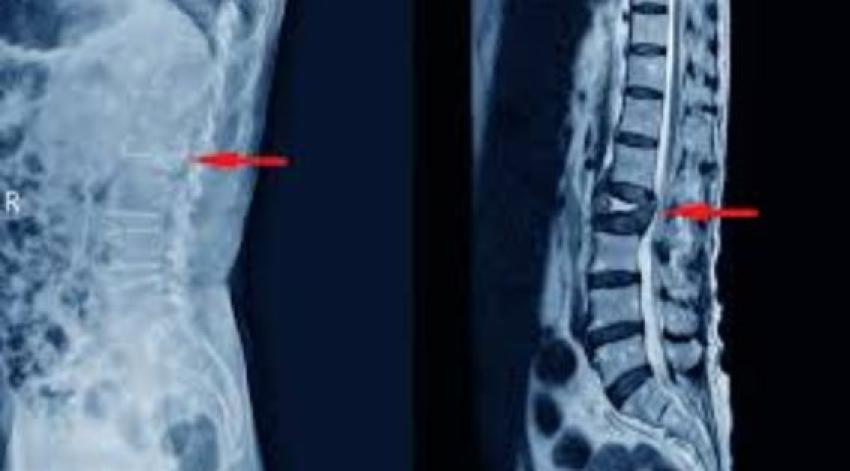

As the Indian population continues to age, bone health is becoming a significant public issue. Osteoporosis, also known as a "silent disease," results in the gradual weakening of bones, such that even a minor fall or simple movement can cause a serious injury. Among the most incapacitating consequences are vertebral fractures that could result in chronic pain, spinal deformity, limited mobility, and the loss of independence. The Osteoporotic spinal fracture India is a topic that has recently been brought about by the increasing number of cases and has gained attention from both medical professionals and the government, thus raising the need for early diagnosis and advanced treatment methods.

One of the foremost issues with spinal injuries due to osteoporosis is that they are usually underdiagnosed. People suffering from these conditions may acknowledge their back pain and loss of height as the effects of ageing only, and therefore, may postpone seeking medical help. The fractures become worse over time without treatment, and this might lead to nerve compression and drastic changes in one's posture.

There is no doubt that the Indian medical fraternity has made significant strides in the area of spine care over the last 20 years. The introduction of minimally invasive surgical procedures such as vertebroplasty and kyphoplasty has revolutionised the way osteoporotic vertebral fractures are treated. They contribute to the stabilisation of the fractured vertebra, eliminate pain more quickly, and thus, pave the way for a quicker return of the patient's normal routine than what was usually the case after major surgery. Additionally, the precision and safety of spine surgeries have been elevated even further through the use of advanced navigation systems, high-resolution imaging, and clinical guidelines.